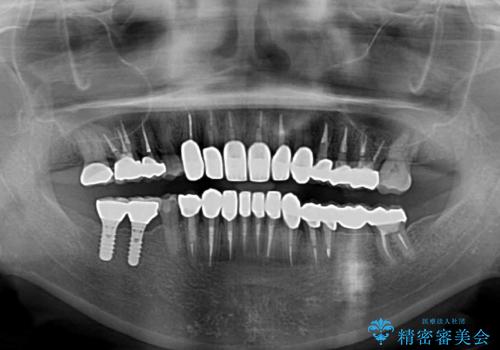

取り急ぎ下顎前歯数歯の根管治療を、銀座しらゆり歯科医院長の林先生にお願いし、それ以外に気になっている、不自然な色調のクラウン、金属部分が見えてブラッシングがしにくいインプラント補綴、口元の突出感、出血のしやすい歯周ポケットなど、全てを解決するための治療を行うこととしました。

期間と費用はかかりましたが、気になっていた部分全てを改善でき、患者様には大変満足していただきました。